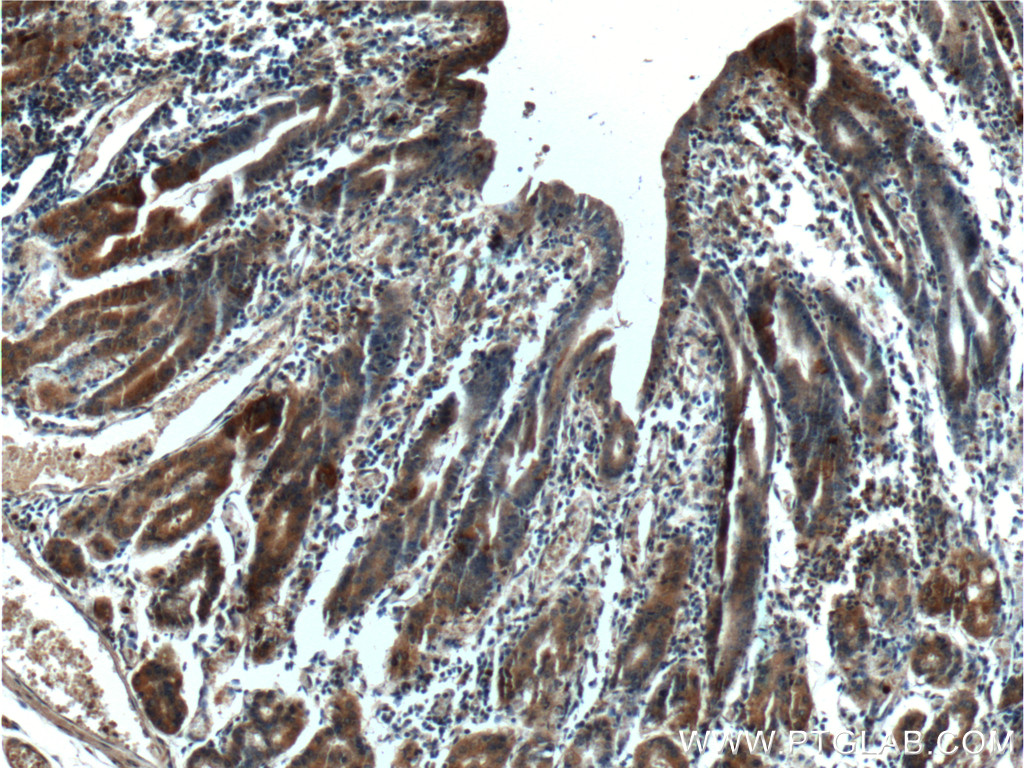

| Positive IHC detected in | human stomach tissue, human liver tissue Note: suggested antigen retrieval with TE buffer pH 9.0; (*) Alternatively, antigen retrieval may be performed with citrate buffer pH 6.0 |

| Immunohistochemistry (IHC) | IHC : 1:50-1:500 |